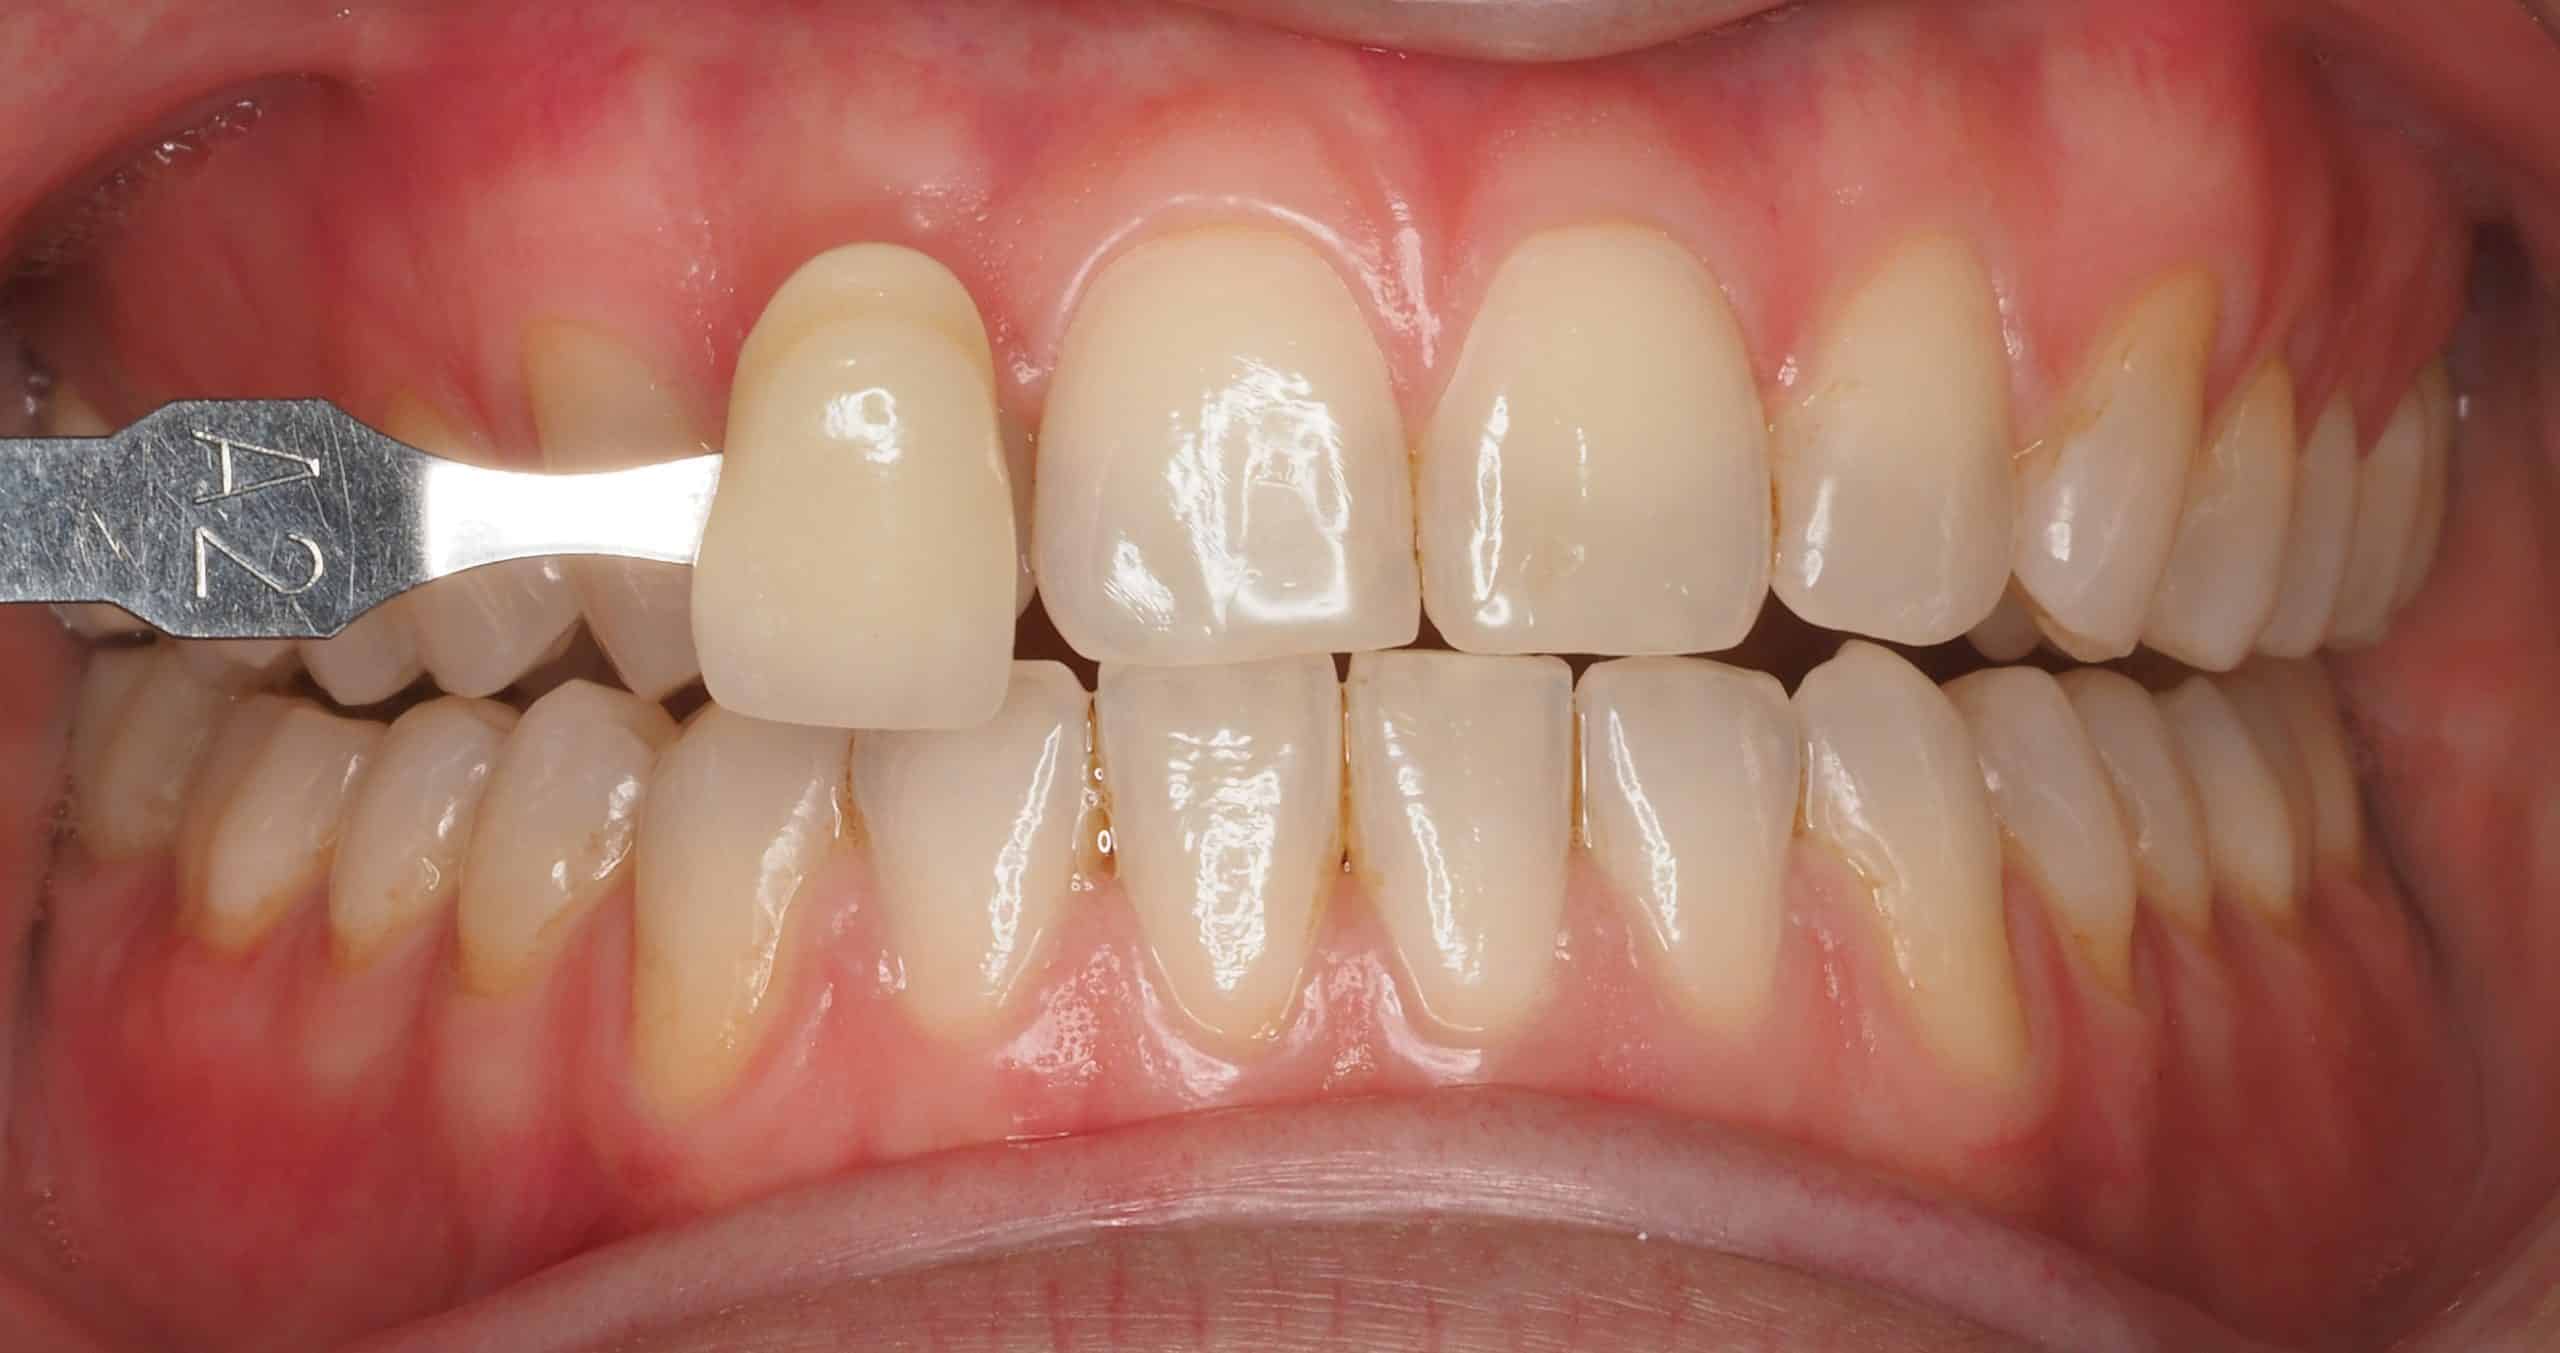

Caso 2

Paciente con dientes desgastados y oscurecidos, se realiza blanqueamiento zoom en una sola sesión.